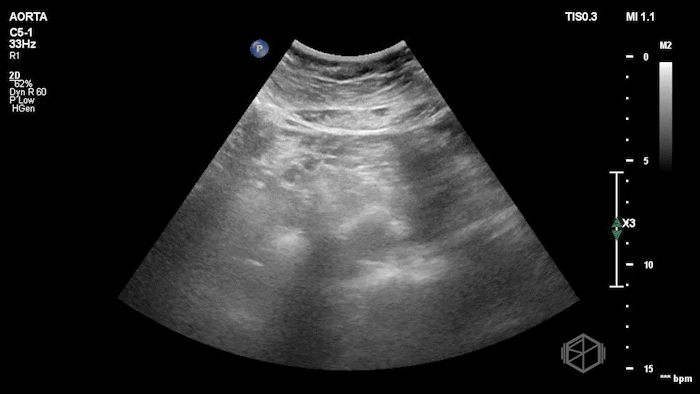

Dr. Singh grabbed the US and saw the following findings:

The POCUS shows a normal sized abdominal aorta, but with a visible flap moving internally. Given the patient has chest pain and near syncope, and extensive dissection was in the differential. Dr. Singh and Dr. Bernot expedited the patient to CTA which showed an extensive Type A aortic dissection. The patient went immediately to surgery and had a positive outcome.

Diagnosis: Type A Aortic Dissection